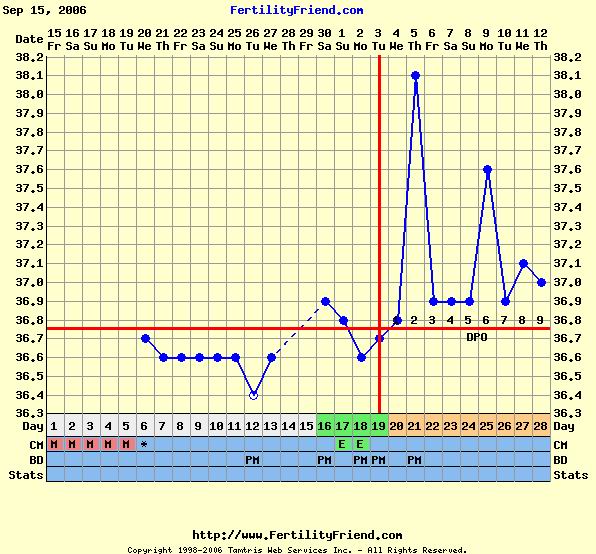

Holnap majd jövök az ideillő görbémmel